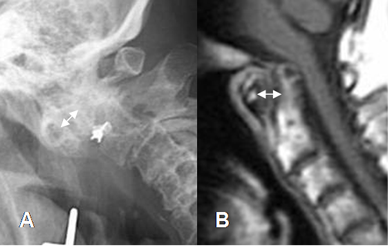

La impactación atlantoaxoidea se caracteriza por desplazamiento vertical de la odontoides. (2). También se pueden encontrar subluxaciones, por el compromiso de las articulaciones interapofisiarias. (2). (Fig 30).

Fig 29 B. Artropatía reumática.

A: Rx lateral y B: RM sagital en T1. Aumento del espacio entre el arco anterior de C1 y la odontoides, por laxitud ligamentaria.